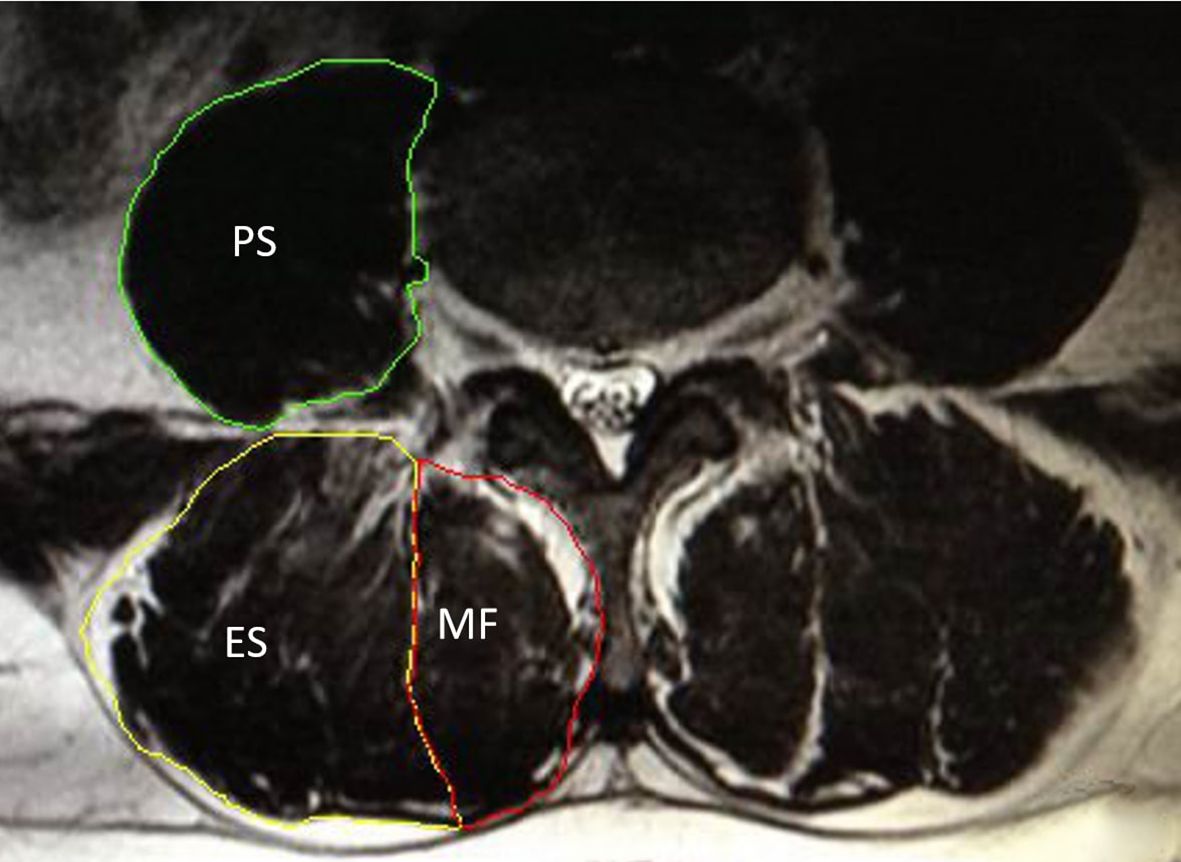

To be included in this meta-analysis, original studies had to meet the following criteria:(1) study types: including cross-sectional studies, cohort studies, case-control studies, and randomized controlled trials that provide original data on the correlation between paraspinal muscle morphometric measurements (such as CSA and FI) and osteoporosis;(2) study subjects: adults (≥ 18 years) of any gender, including patients diagnosed with osteoporosis and healthy controls or those with normal BMD;(3) paraspinal muscle measurements: studies must report morphometric data of at least one paraspinal muscle (e.g., multifidus, erector spinae, psoas major, see Figure 1), primarily focusing on CSA and FI, as well as derived quantitative indices. For CSA, only studies using manual or semi-automated segmentation were included, given the limited accuracy and clinical validation of fully automated methods (33). Inter- observer and intra-observer reliability data were not required for inclusion, given that such metrics were often unreported in studies. (4) osteoporosis diagnosis: studies must specify diagnostic criteria for osteoporosis (e.g., based on BMD T-scores or quantitative computed tomography bone volume);(5) language: Chinese and English publications.

Figure 1

Axial MRI at the lumbar level showing segmentation of paraspinal muscles: psoas major (PS), erector spinae (ES), and multifidus (MF).